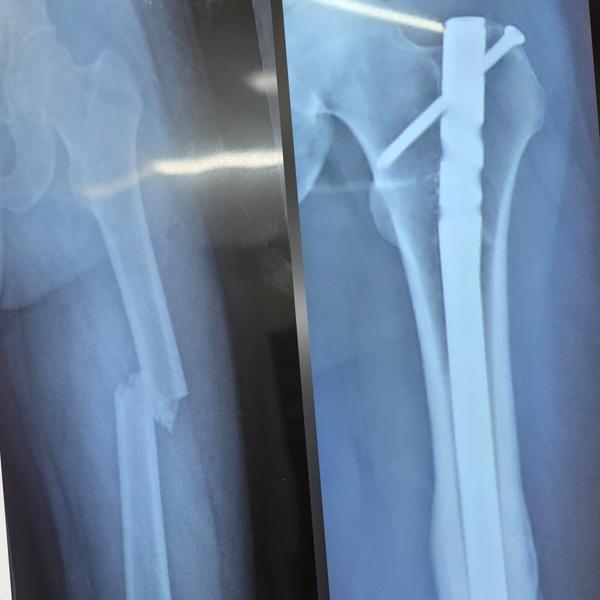

Intertrochatric fracture of hip